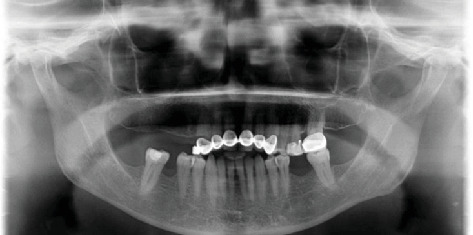

前言:种植牙科作为治疗缺牙患者康复的首选,其需求日益增长。临床医生可以在无牙空间遇到无症状的保留根碎片。本病例报告介绍了种植体晚期失败的长期预后,种植体放置11年后仍有根残余附着在固定装置上。病例报告:一名68岁女性患者在首次植入种植体11年后,因上颌右侧四单元种植体支撑桥功能相关而就诊。拔除修复体后,发现残根附着在中间支撑种植体的固定物上。种植体无意中侵占了残根碎片的中间部分,这是在拔桥时意外发现的。结论:考虑到潜在的阻碍骨整合的风险,临床医生在种植体中使用保留的根残余物时应格外注意。然而,被侵占的种植体和根碎片的骨整合是合理的,没有观察到有害的短期影响。风险-收益评估应该单独评估,因为后期失败仍然可能发生。试验注册:ClinicalTrials.gov标识符:NCT06671678。

Introduction: There is a growing demand for implant dentistry as the first choice of rehabilitation for treating patients with missing teeth. Clinicians can encounter asymptomatic retained root fragments in edentulous spaces. This case report presents the long-term prognosis of an implant resulting in late failure, with an attached root remnant to the fixture 11 years after implant placement. Case Report: A 68-year-old female patient presented to the clinic with complaints of function related to a maxillary right four-unit implant-supported bridge 11 years after the first insertion of the implants. After the removal of the restoration, a root remnant was found as adhered to the fixture of the middle supporting implant. The implant was placed encroaching upon the mesial part of the residual root fragment left unintentionally, which was discovered accidentally during the bridge removal. Conclusion: Clinicians should show ultimate attention when utilizing the retained root remnants in implant sites, considering the potential risk of hindering osseointegration. However, osseointegration of the encroached implant and root fragment is plausible, with no detrimental short-term impacts observed. A risk-benefit evaluation should be assessed individually, as late failures can still occur. Trial Registration: ClinicalTrials.gov identifier: NCT06671678.